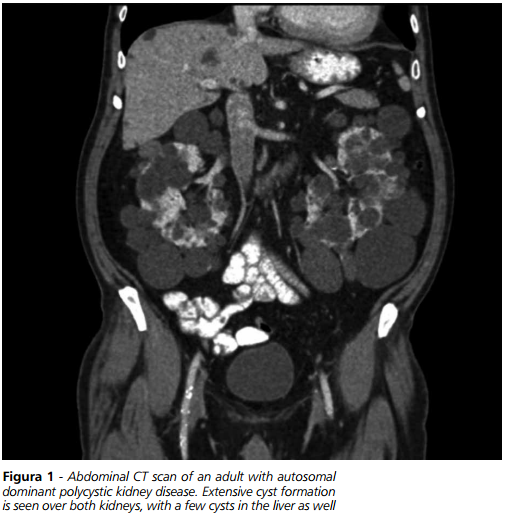

MINETTI – Il rene policistico autosomico dominante (ADPKD) per i nefrologi rappresenta una patologia di grande interesse, essendo la più frequente condizione ereditaria che interessa il rene, caratterizzata da una evoluzione progressiva verso l’insufficienza terminale di organo. Colpisce circa 4 persone ogni 10.000 ed in questo senso può essere considerata una malattia “rara”, anche se i riscontri autoptici parlano di cifre molto più alte a causa del grande numero di casi che rimangono asintomatici in relazione alla penetranza della malattia. La forma più frequente, riscontrata in circa l’85% dei pazienti, è quella autosomica dominante in cui si ha una mutazione che interessa il gene posto sul cromosoma 16 che codifica per una proteina chiamata appunto policistina. Il restante 15% dei casi si riferisce ad una alterazione di un gene posto sul cromosoma 4 che codifica per un’altra proteina definita policistina 2. A questi due quadri di alterazione genetica si legano i differenti comportamenti nell’andamento clinico della malattia.

Inoltre non dobbiamo dimenticare che la localizzazione renale della malattia policistica in circa il 5 - 6% dei pazienti può essere riscontrata anche in altri organi come il fegato o le arterie cerebrali dove si ritrova il cosiddetto aneurisma di Berry, che in seguito a rottura può indurre emorragia cerebrale e morte prematura.

MINETTI – Un aspetto importante da valutare quando si esaminano le potenzialità di una nuova molecola è certamente rappresentato dalla selezione dei pazienti nei quali impiegarlo. Come già detto un criterio di valutazione importante nella stadiazione della malattia policistica renale è la misurazione del volume del rene o dei reni interessati. Oltre alle normali metodiche radiologiche che ne misurano i diametri antero-posteriore, longitudinale o trasverso, disponiamo oggi di metodiche TAC che, basate sull’impiego di appositi software, riescono a misurare con grande esattezza il reale volume dell’organo malato. Si tratta di tecniche ancora non del tutto entrate nella comune pratica clinica, che comunque necessitano della collaborazione partecipata di radiologi specificamente a conoscenza dei diversi aspetti della malattia.